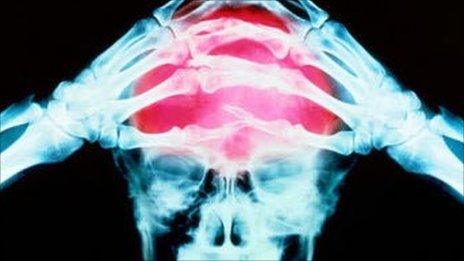

Health services for people with neurological conditions in England are not good enough, says a report from a committee of MPs.

It criticises poorly co-ordinated local services, patchy hospital care and long delays in diagnosing conditions like Parkinson's disease and epilepsy.

More than four million people have a neurological condition but few have a care plan, the report says.